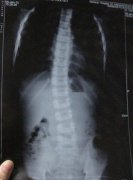

• 治好强直性脊柱炎,去圆自己大学梦

季先生自患有强直性脊柱炎后,一直积极接受治疗。在经过2年的无 ...